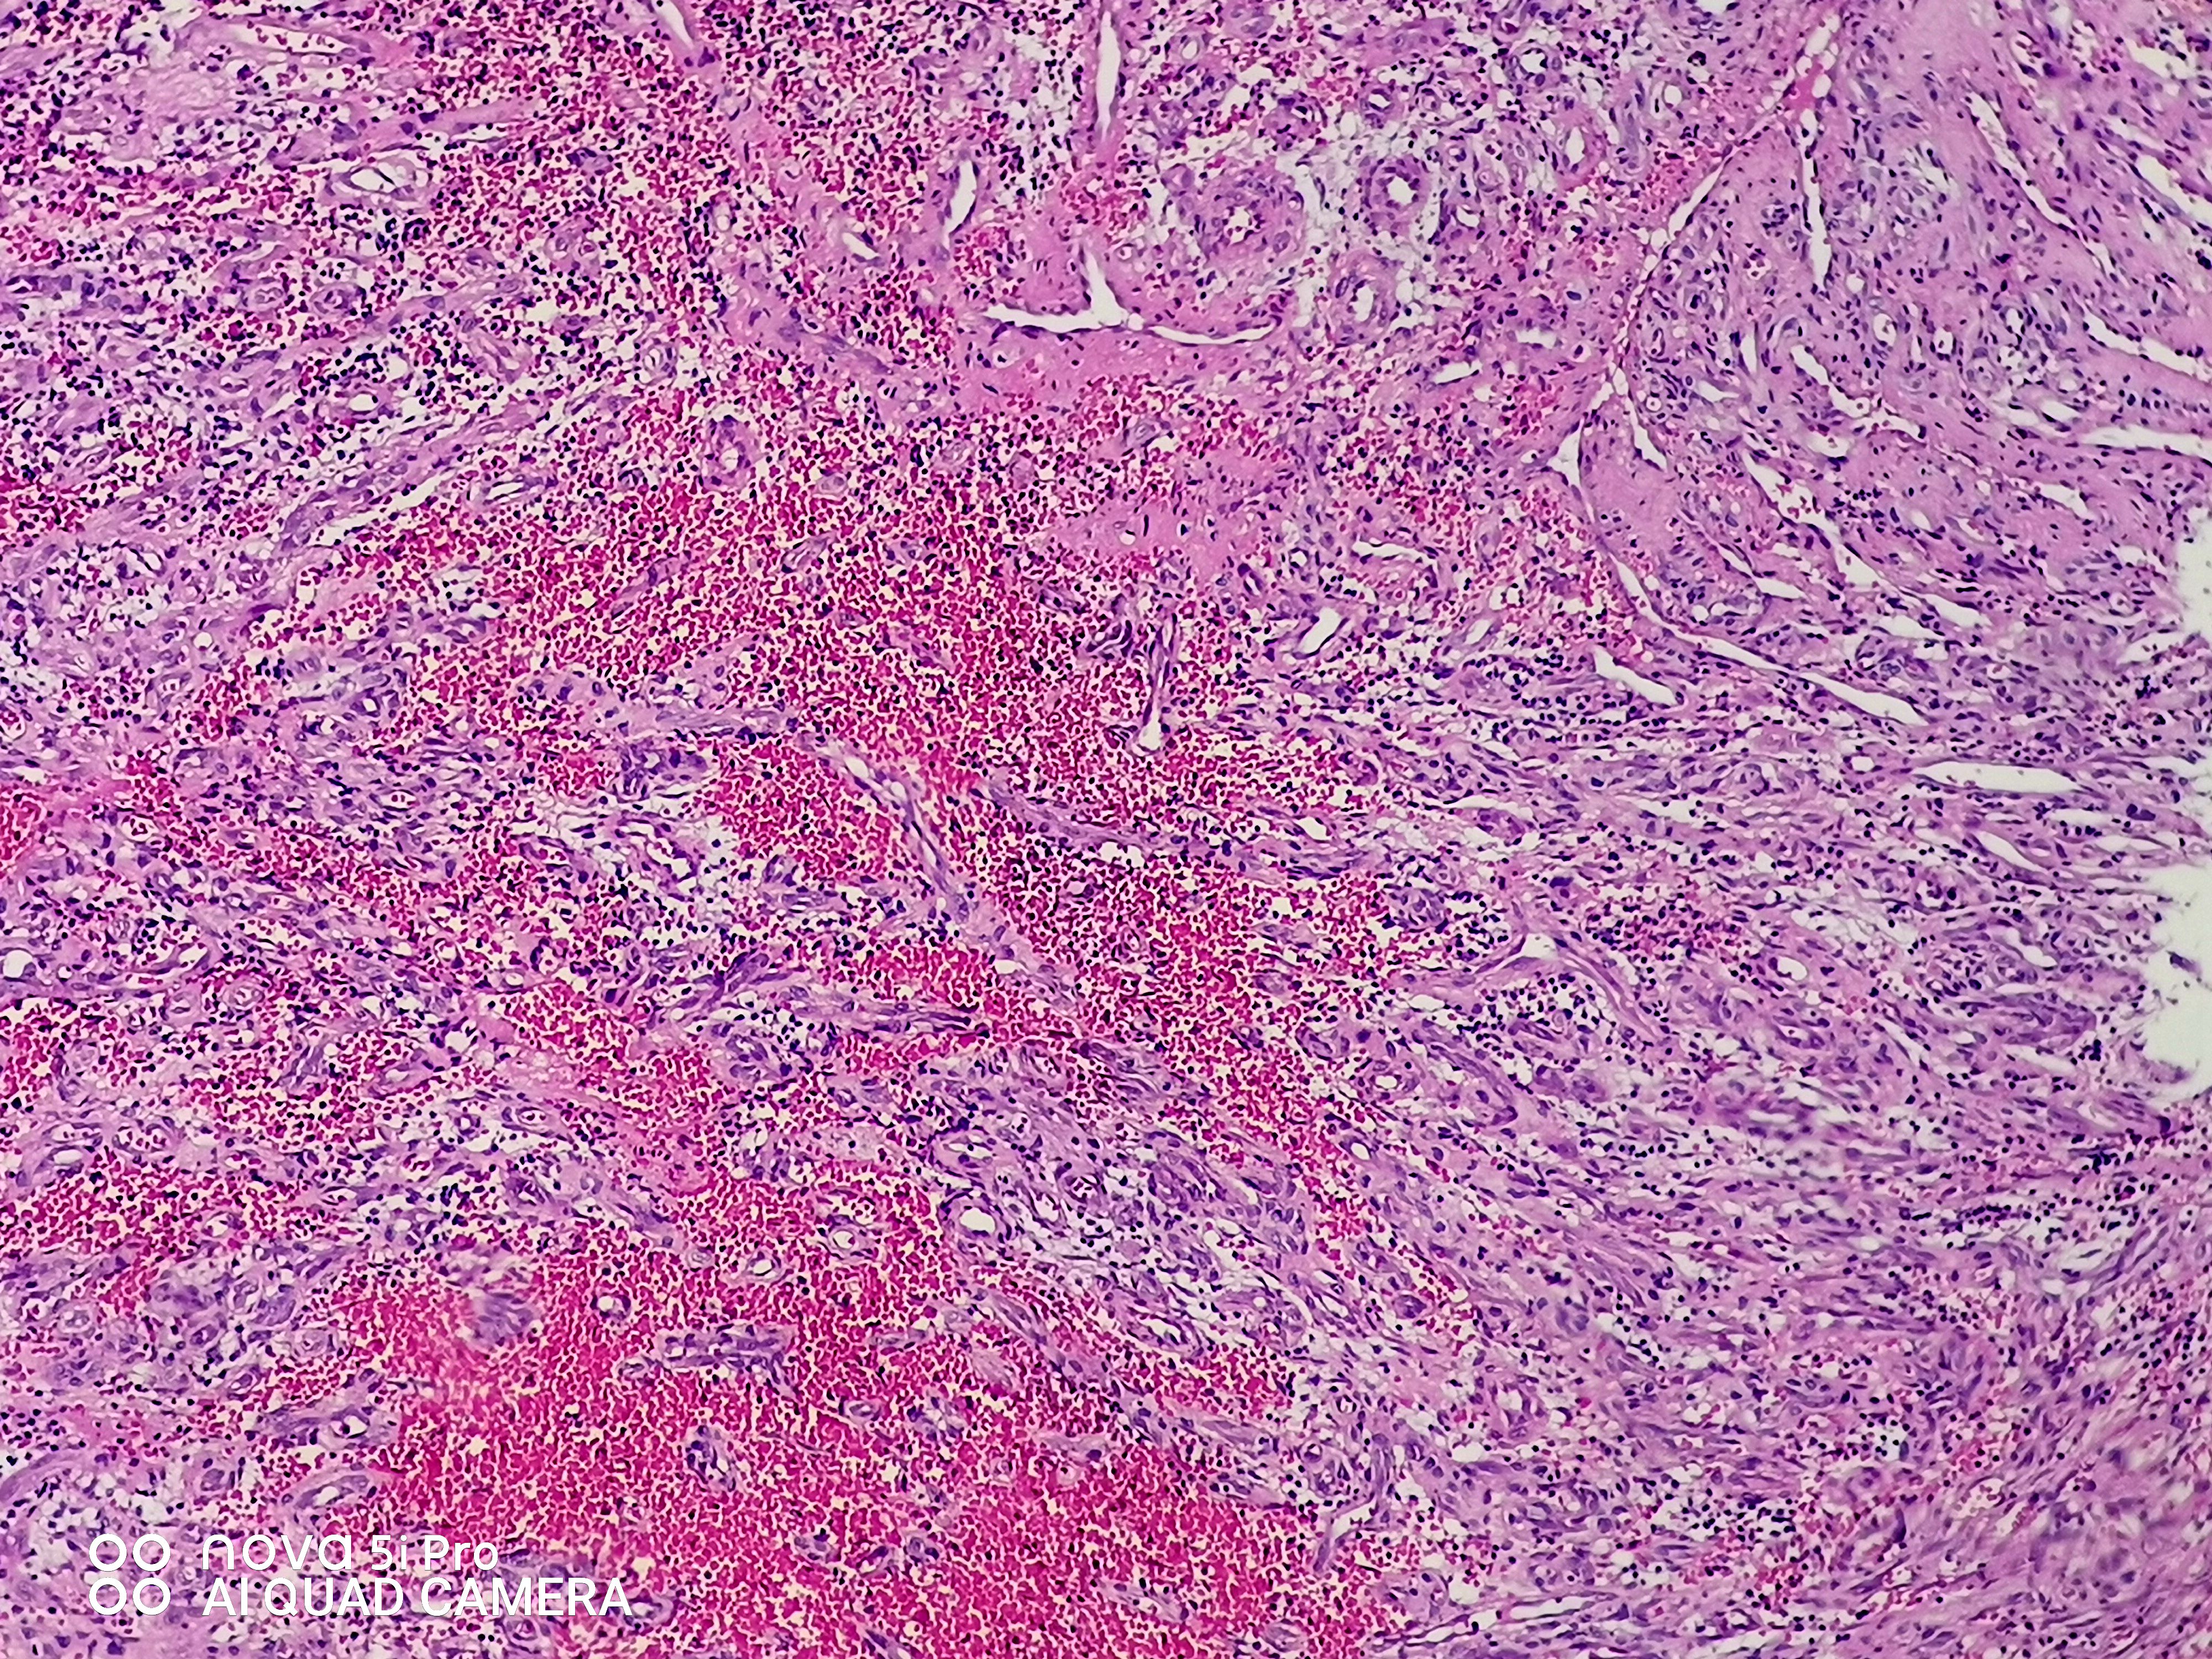

请老师们看看这个足跟肿块,血管瘤?谢谢了!

性别

女

年龄

43岁

临床诊断

待查

一般病史

发现左足跟肿块一年余

标本名称

左足跟肿块

大体所见

组织一块,大小约1.6*1.0*0.6cm,切开,实性灰白夹褐质中,一盒全取。

肉芽肿性毛细血管瘤。